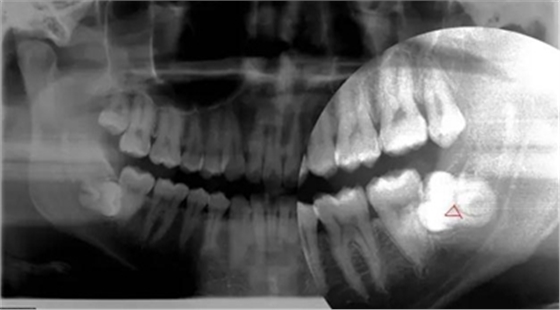

智齒水平阻生(長橫過來了),影響前面牙齒或者致前面牙齒擁擠不齊